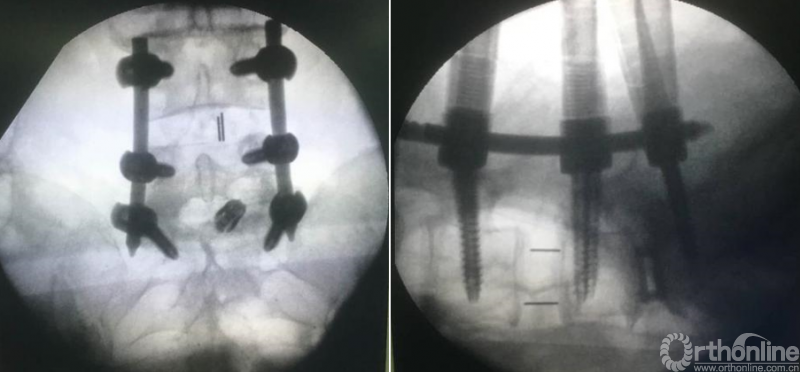

第九步“填”;椎间隙填塞植骨;

第十步“置”:置入融合器、经皮钉。